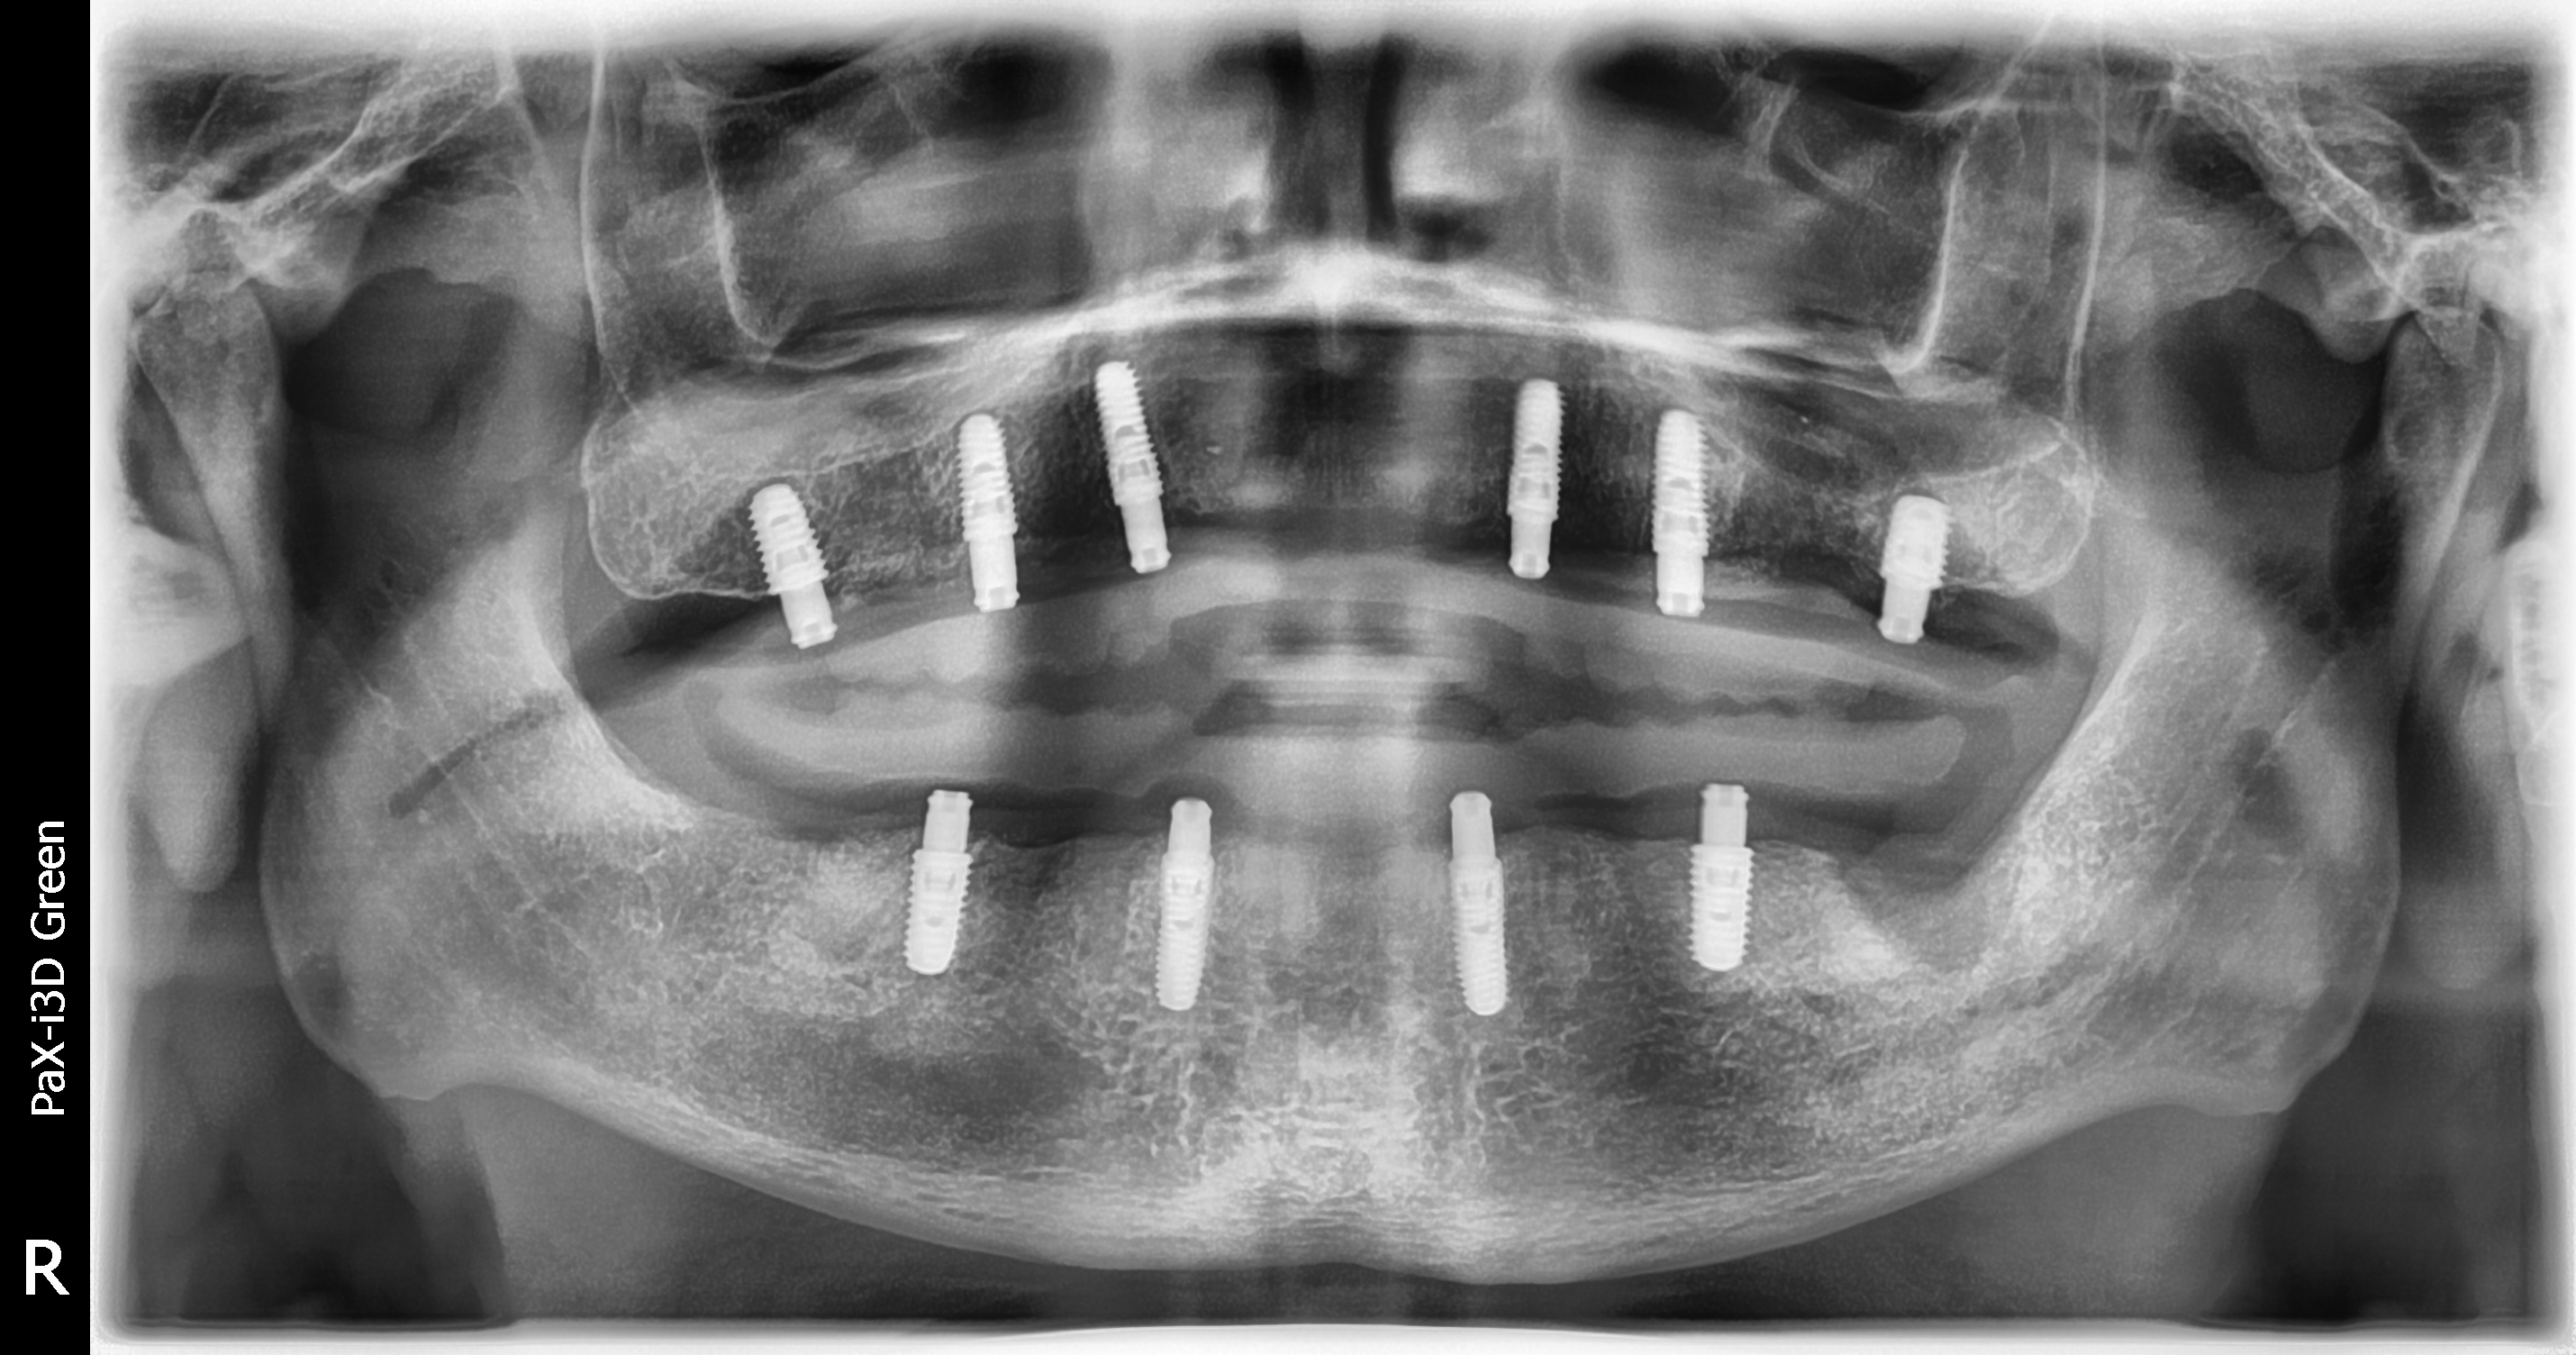

A 45-year-old man presented with a failing dentition (Figure 6). After a comprehensive analysis of his dentition, a cone beam computed tomography scan (Green CT, Vatech America) confirmed that the patient had bone quality and quantity sufficient for several different implant positions (Figure 7). Multiple treatment options were discussed with the patient, including complete dentures, implant overdentures, and fixed hybrid restorations. The patient indicated that he greatly preferred the fixed hybrid restorations, as he was not happy with the idea of removable dentition. After an extensive clinical and financial discussion, the patient concluded that fixed hybrid treatment was beyond his budget and requested implant overdenture treatment. He did inquire about the possibility of changing from the overdenture to the fixed hybrid later if his financial situation changed.

As a result of this discussion, a treatment plan of six implants on the maxillary arch and four implants on the mandibular arch was presented. The patient agreed to the treatment, and the teeth were extracted and dental implants (ET III, Hiossen) were placed in the tooth No. 2/3, 4/5, 7, 10, 13/14, 14/15 positions on the maxillary arch and the tooth No. 19, B, D, 30 positions on the mandibular arch. After osseointegration, definitive stud-style abutments (LOCATOR R-Tx) were placed and torqued according to the manufacturer's recommended torque value on implants in the maxillary and mandibular arches (Figure 8 and Figure 9).

Fig 7. A cone-beam computed tomography scan (Green CT, Vatech America) showed that the patient had an abundance of bone quality and quantity for six implants on the maxillary arch and four implants on the mandibular arch. Implants were placed in positions that would allow a fixed restoration at a later date.

Figure 7